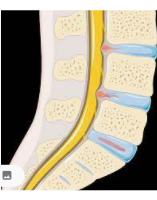

척추탈위증은 앞으로 척추체가 미끄러져 나오는 증상입니다. 보통 허리뼈 L4-5-S1에서 주로 발생되며 척추관의 협착증을 동반합니다.

척추관이 협착되는 경우에는 허리통증이 발생하면서, 머리부터 다리까지 신경이 지나가는 통로가 좁아지기 때문에 감각이 점점 없어지고 저린감이 광범위하게 심해집니다.

주원인은 퇴행성 변화로 감압술을 시행하는 경우가 대다수 입니다.